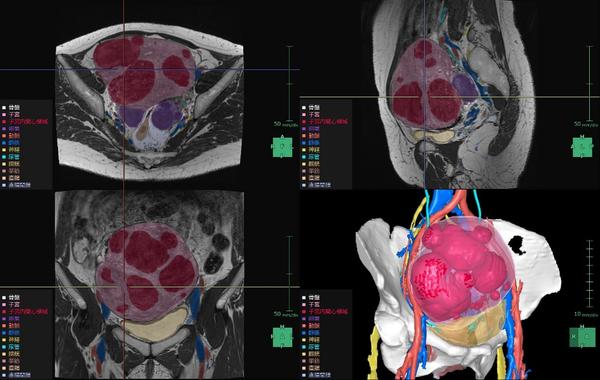

子宮筋腫は,成人女性の罹患率が20~30%と高頻度に見られる疾患*4で,機能温存が重要とされている。MRIや超音波画像診断装置の2D画像では筋腫や周囲組織の3次元的な把握が難しく,骨盤内の複雑な解剖構造の理解も困難。また,筋腫の大きさや数,妊孕性温存の希望などにより様々な手技が適用されるが,筋腫の計測や手技の選択は各医師の経験則や感覚に基づいて行われているという課題がある。「婦人科臓器解析」ではMRIのT2画像からAI技術*2を活用した抽出エンジンを用いて子宮周囲の臓器をセグメンテーションし,ユーザーが子宮筋腫と判断した箇所の体積・数・深さの定量化を行うことができる。また,3Dで周辺組織との位置関係を把握することで筋腫手術の低侵襲化や取り残し防止等への寄与が期待される。

婦人科臓器解析の解析画面